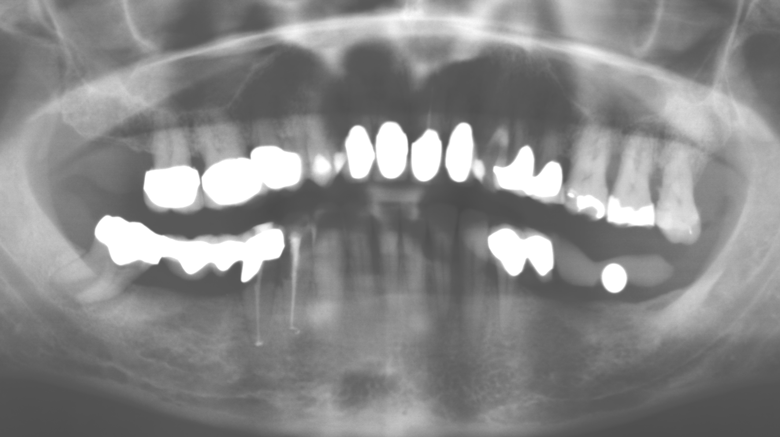

Für den klinischen Langzeiterfolg des parodontal kompromittierten Patienten ist die standardisierte und regelmäßige risikoadaptierte Betreuung im Rahmen der UPT der zentrale Baustein des Behandlungserfolgs. Dies gilt in besonderer Weise für Patienten, die nach erfolgreich abgeschlossener parodontaler Sanierung mit Implantaten versorgt wurden (Abb. 11a und b).

Die Patientin befindet sich weiterhin in einem halbjährlichen Intervall für die UIT. Nachfolgend werden am Beispiel dieser Patientin die einzelnen Arbeitsschritte einer strukturierten UPTSitzung aufgezeigt, so wie sie nahezu unverändert über den gesamten Funktionszeitraum von immerhin zwölf Jahren durchgeführt wurden. Natürlich wurden über diesen Zeitraum einige neue Materialien und Geräte in das Konzept integriert. In diesem klinischen Fallbericht wird das aktuelle Material und Gerätekonzept präsentiert.